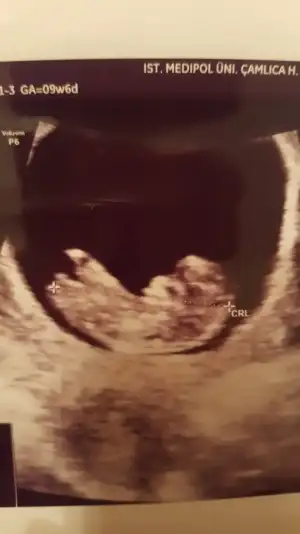

Merhabalar Tahmin yorumlarınızı heyecanla takip ediyorum. Bende sabırla 12. haftamızın dolmasını bekledim. Bir yorumda benim için yaparmısınız Buğün 12+1 olduk.